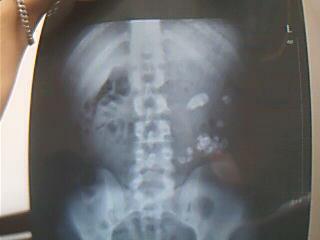

现龄21岁,男,左肾有很多结石,其中最大的有3.7x2.1CM ,2.1x1.7CM其中1CM左右的很多,还有其他像米粒大小的,有中等程度的积水,实质变薄,体积增大。(X光 和B超都是同样的结果)。左输尿管上段扩张内径约1.2CM,内可见范围约1.2x0.7CM的强回声团,后伴声影,中下段气体干扰显示不清。右肾正常。